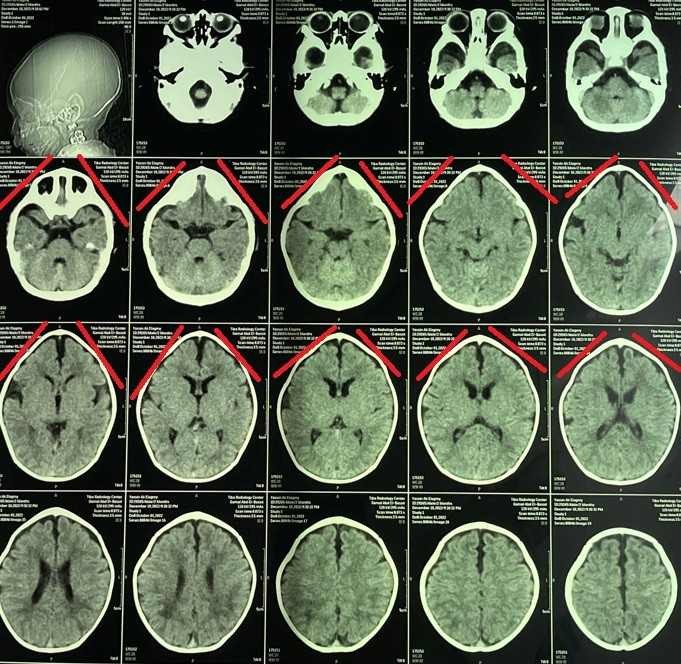

Trigonocephaly Correction Surgery in a Two-Month-Old Infant

A successful cranial correction surgery was performed on a two-month-old infant suffering from trigonocephaly, a condition characterized by a triangular-shaped head. This type of cranial deformity results in a triangular head appearance with a prominent forehead ridge. The goal of the surgery was to correct the skull shape to ensure normal brain development and protect the child from future complications.

• Precise pre-operative planning using 3D imaging